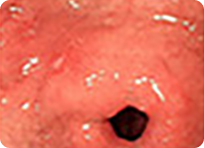

매우 작고 미세한 변화만을 보이는 조기위암들

풍부한 내시경 경험을 가진 의료진이 최신의 내시경 기계를 이용하여 세심한 관찰을 해야 위와 같은 매우 작은 조직 위암을 놓치지 않고 진단할 수 있습니다.

조기 위암의 경우 대부분 증상이 없으며 증상이 있어도 단순한 속 쓰림이나 소화불량증과 구별이 안됩니다.

전문가에 의한 위내시경 검사는 수 mm 크기의 조기 위암도 정확히 진단할 수 있습니다. 특히 색소를 이용한 색소 내시경의 경우 육안적으로 구별하기 힘든 병변도 정확히 진단할 수 있습니다.

조기 위암